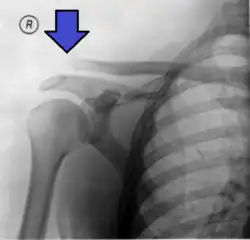

| An Xray showing a separated shoulder. Notice the separation between the end of the collarbone and the scapula. | |

A separated shoulder, also known as acromioclavicular joint injury, is a common injury to the acromioclavicular joint.[2] The AC joint is located at the outer end of the clavicle where it attaches to the acromion of the scapula.[2] Symptoms include non-radiating pain which may make it difficult to move the shoulder. The presence of swelling or bruising and a deformity in the shoulder is also common depending on how severe the dislocation is.[2][1]

X-ray indicates a separated shoulder when the acromioclavicular joint space is widened (it is normally 5 to 8 mm).[9]

This is a more severe form of a type III injury, with the trapezial and deltoid fascia stripped off of the acromion as well as the clavicle. This is type III but with exaggeration of the vertical displacement of the clavicle from the scapula. There is a 2- to 3-fold increase in the coracoclavicular distance, causing such a severe displacement that the clavicle almost pierces the skin.[11] The humerus and scapula drop without having the clavicular strut to lift them, which manifests as a severely drooping shoulder.[11] This injury generally requires surgery.[5] Distinguishing between Type III and Type V separations on imaging can be unreliable.[12]